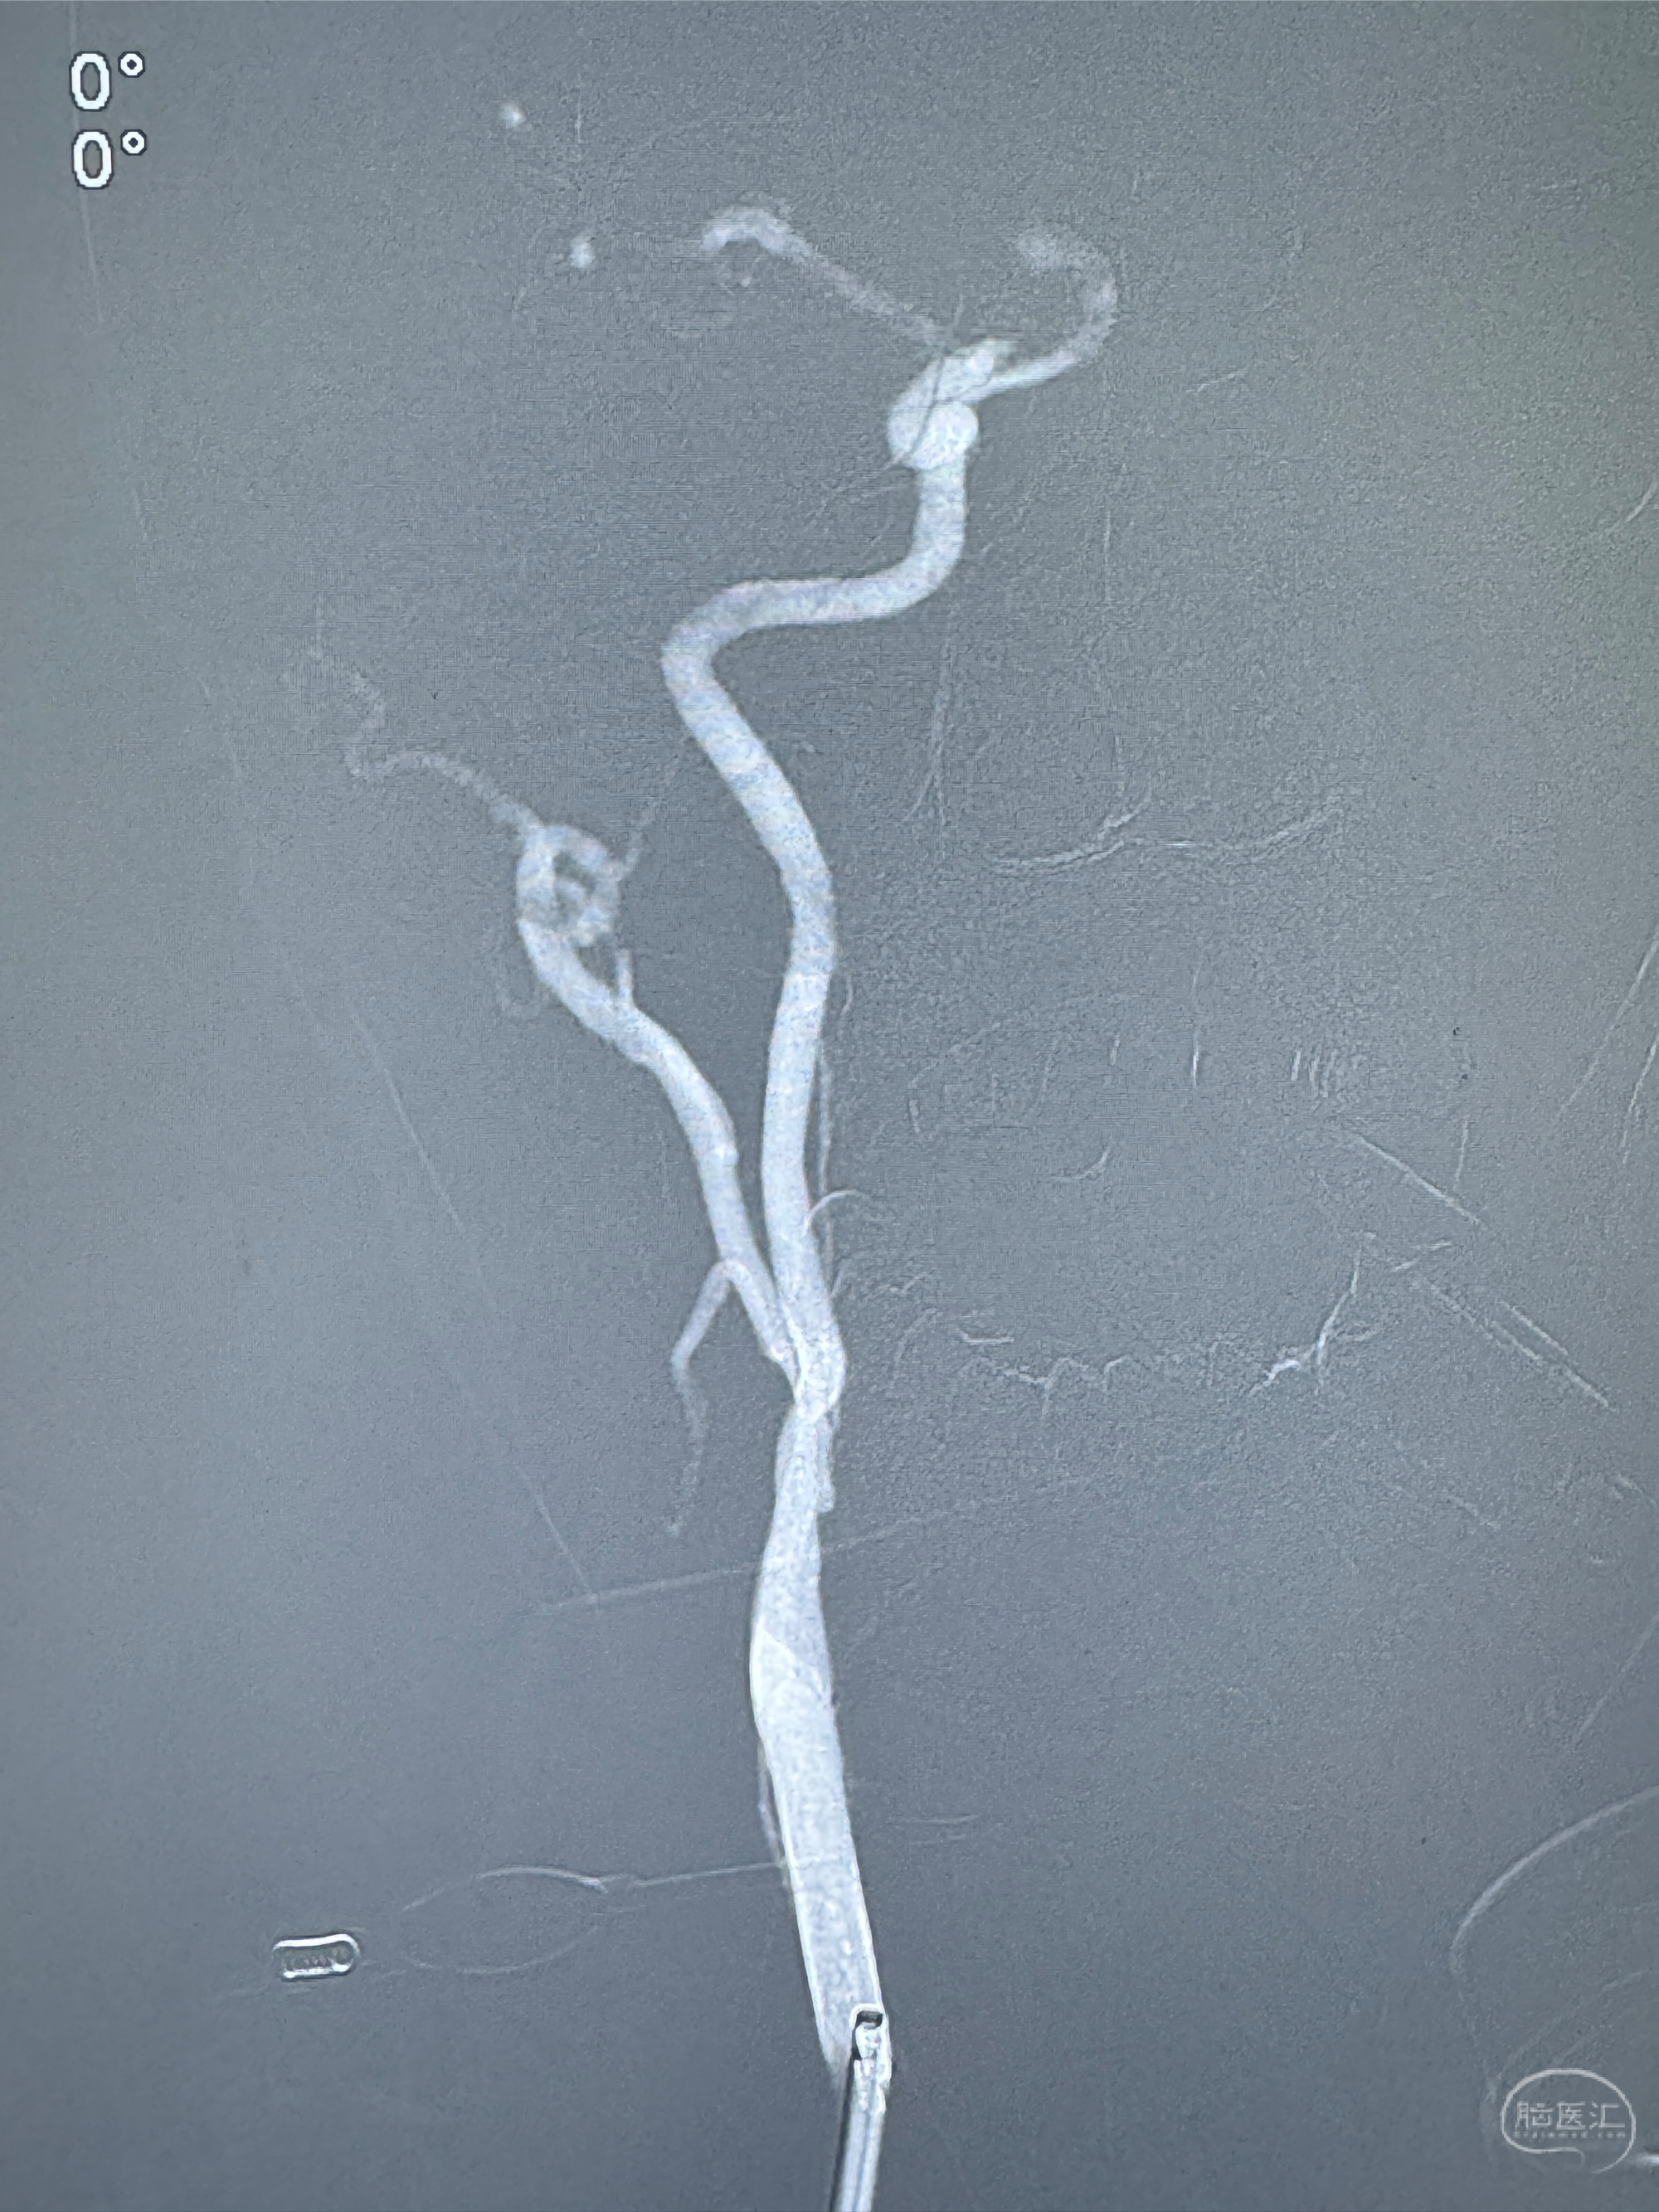

2023-12-27术后第十天复查DSA

支架贴壁佳,但可见射流,咋办?

2024-01-08全麻下再行植入密网支架一枚

Tubridge 4.5-35mm

支架植入顺利,贴壁佳,支架内血流通畅,动脉瘤内血液滞留明显